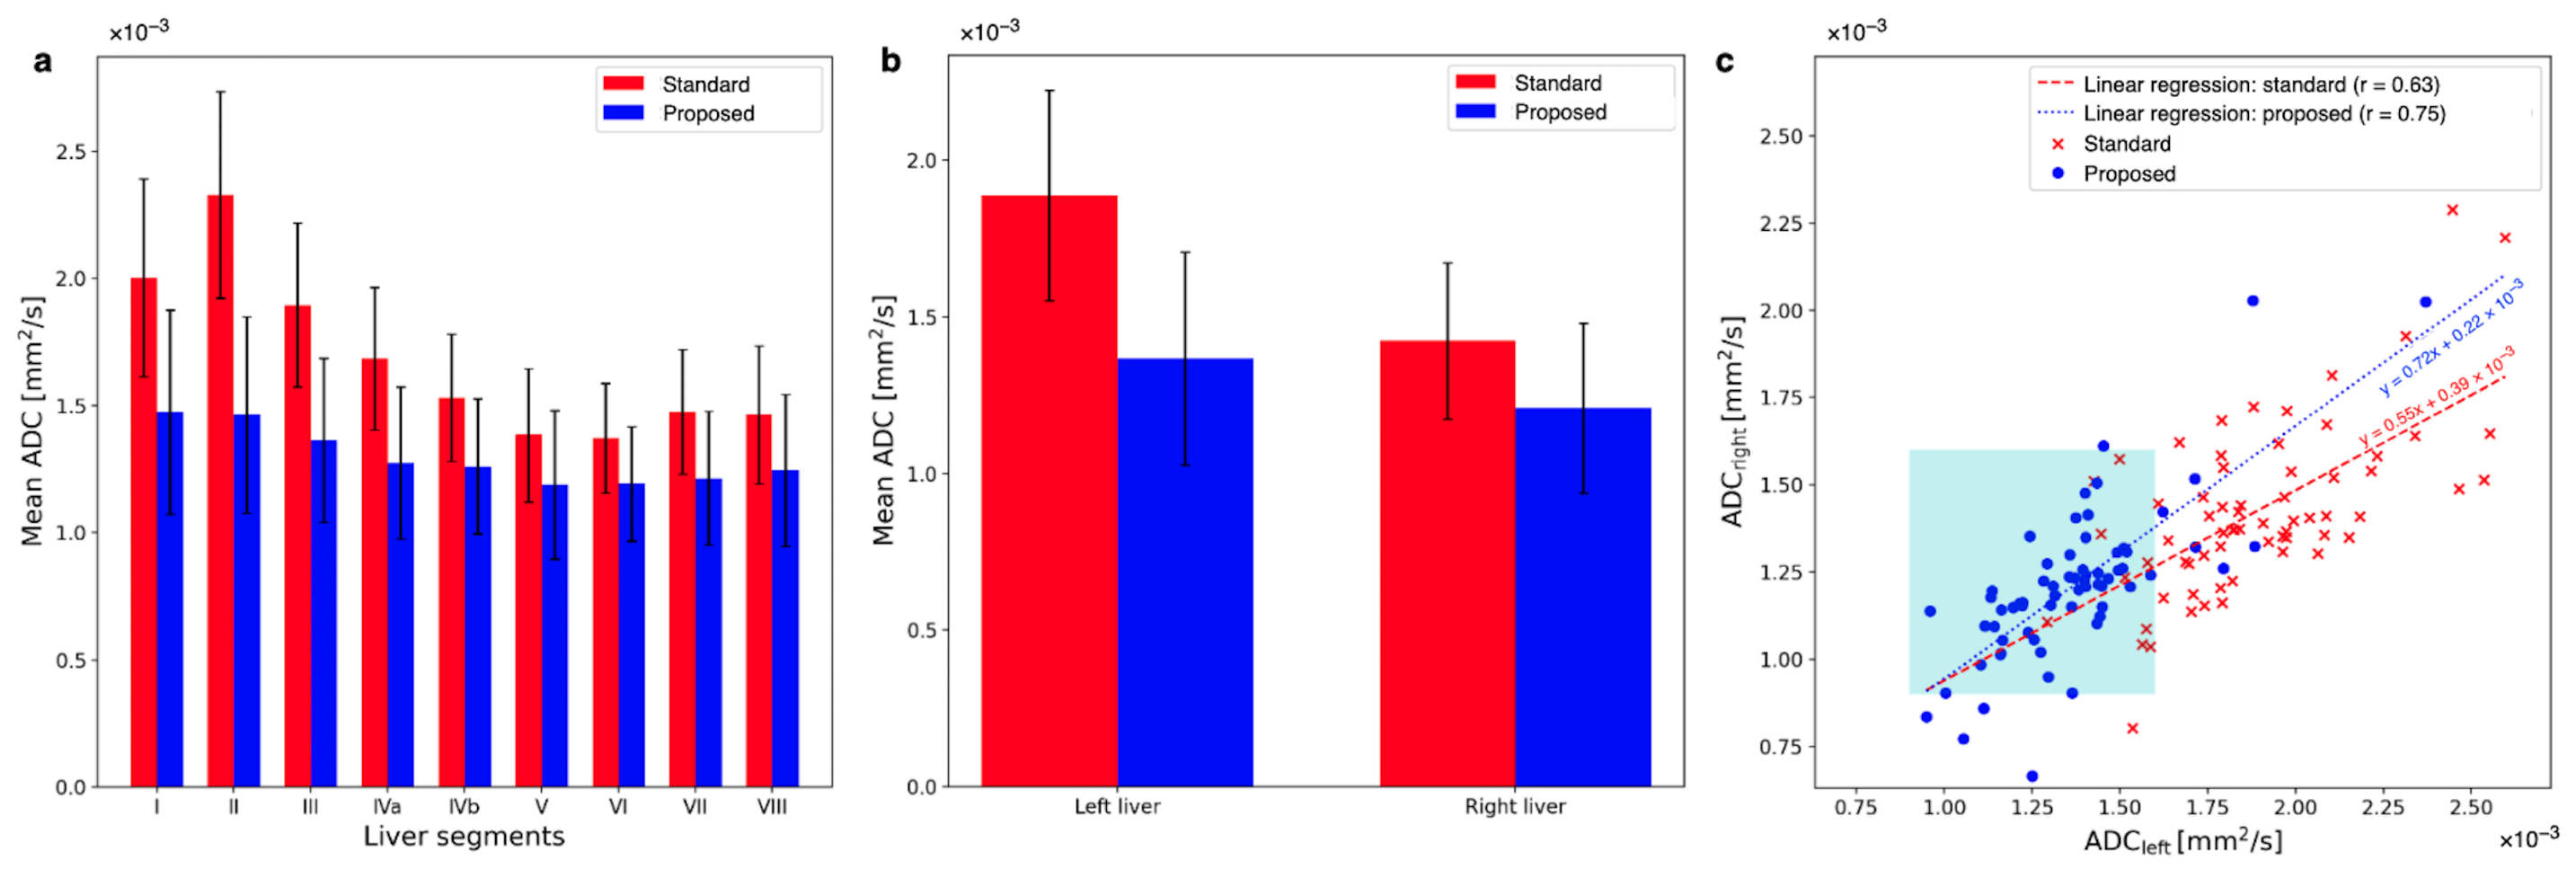

3.3. Quantitative ADC Measurement

3.4. Radiological Reading